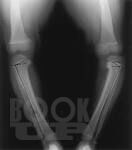

В учебном пособии подробно освещены вопросы эмбриогенеза трубчатых костей, нарушения их развития и формирования, дана подробная классификация нарушений дизонтогенеза. Описаны основные нозологические формы дизонтогенетических нарушений, наблюдаемых в клинической практике. Освещены вопросы кровоснабжения длинных трубчатых костей и репаративной регенерации при их переломах.